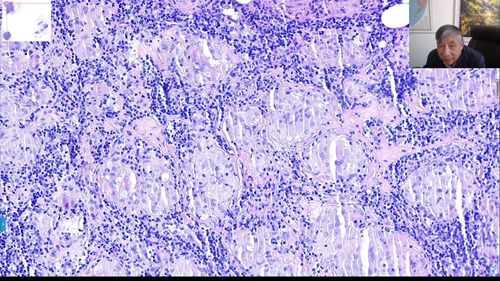

小土豆跟着农人老师学本领-胃窦活检+几个不对称腺管位于粘膜肌+腺癌

2023年04月02日 1429 03分46秒